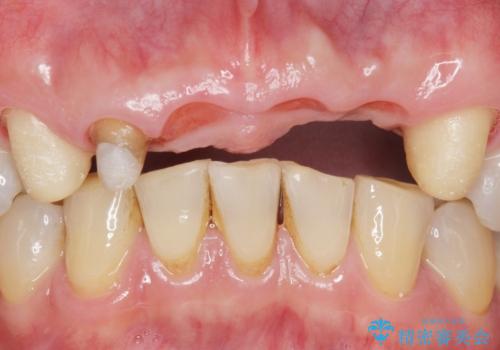

- お風呂場で転んで上の前歯が2本抜けてしまったことを主訴に来院された患者様です。

精査したところ、左上の側切歯(左上2)も破折しており保存不可能な状態でした。

左上の側切歯(左上2)を抜去し、右上の側切歯(右上2)の再根管治療後、セラミックのブリッジによる補綴を行いました。

- ¥770,000 (根管治療×1本、土台×1本、仮歯×6本、クラウン×6本)費用は治療当時の料金となります